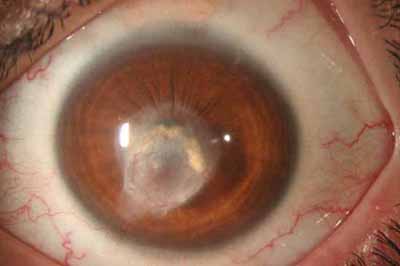

En su evolución se observará aumento del edema, aparición de un anillo inmunológico (Wessely), agrandamiento y coalescencia de los infiltrados que progresan hacia la formación de un absceso, queratolisis superficial, adelgazamiento y perforación corneal.

Anillo inmunológico de Wessely

- Es la expresión de la interacción de los antígenos extraños con los anticuerpos que se difunden desde los vasos limbares hacia el estroma.

- Representa la formación de un complejo inmune que activa el sistema del complemento.

- El anillo de Wessely contiene principalmente neutrófilos

- Puede aparecer en procesos no infecciosos